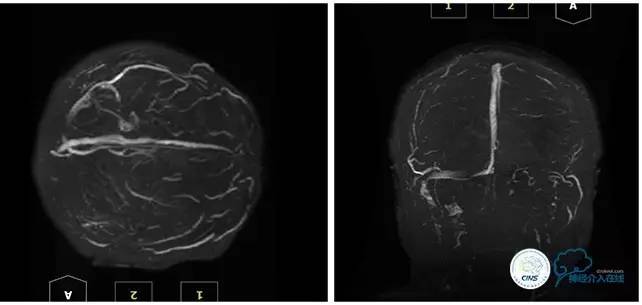

MRV

诊断:1、右侧横窦、乙状窦狭窄;2、硬膜下血肿(左侧顶);3、继发性癫痫;4、脑脊液鼻漏;5、颅内感染;6、乳突炎;7、鼻窦炎。

2016-05-20 MRV